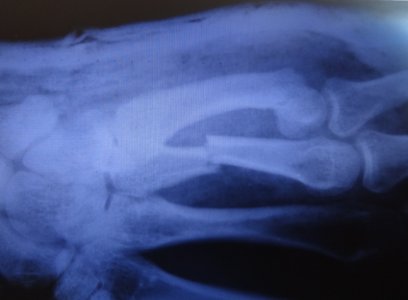

Обратился к травматологу по месту жительства и на 6 день после получения травмы сделали контр.снимок:

Доктор взглянув на НЕЗНАЧИТЕЛЬНОЕ СМЕЩЕНИЕ сказал что нужна репозиция, сделал закрытую репозицию отломков и наложил лонгету на 4 и 5 пальцы в вытянутом состоянии, вот снимки сразу после наложения лонгеты: